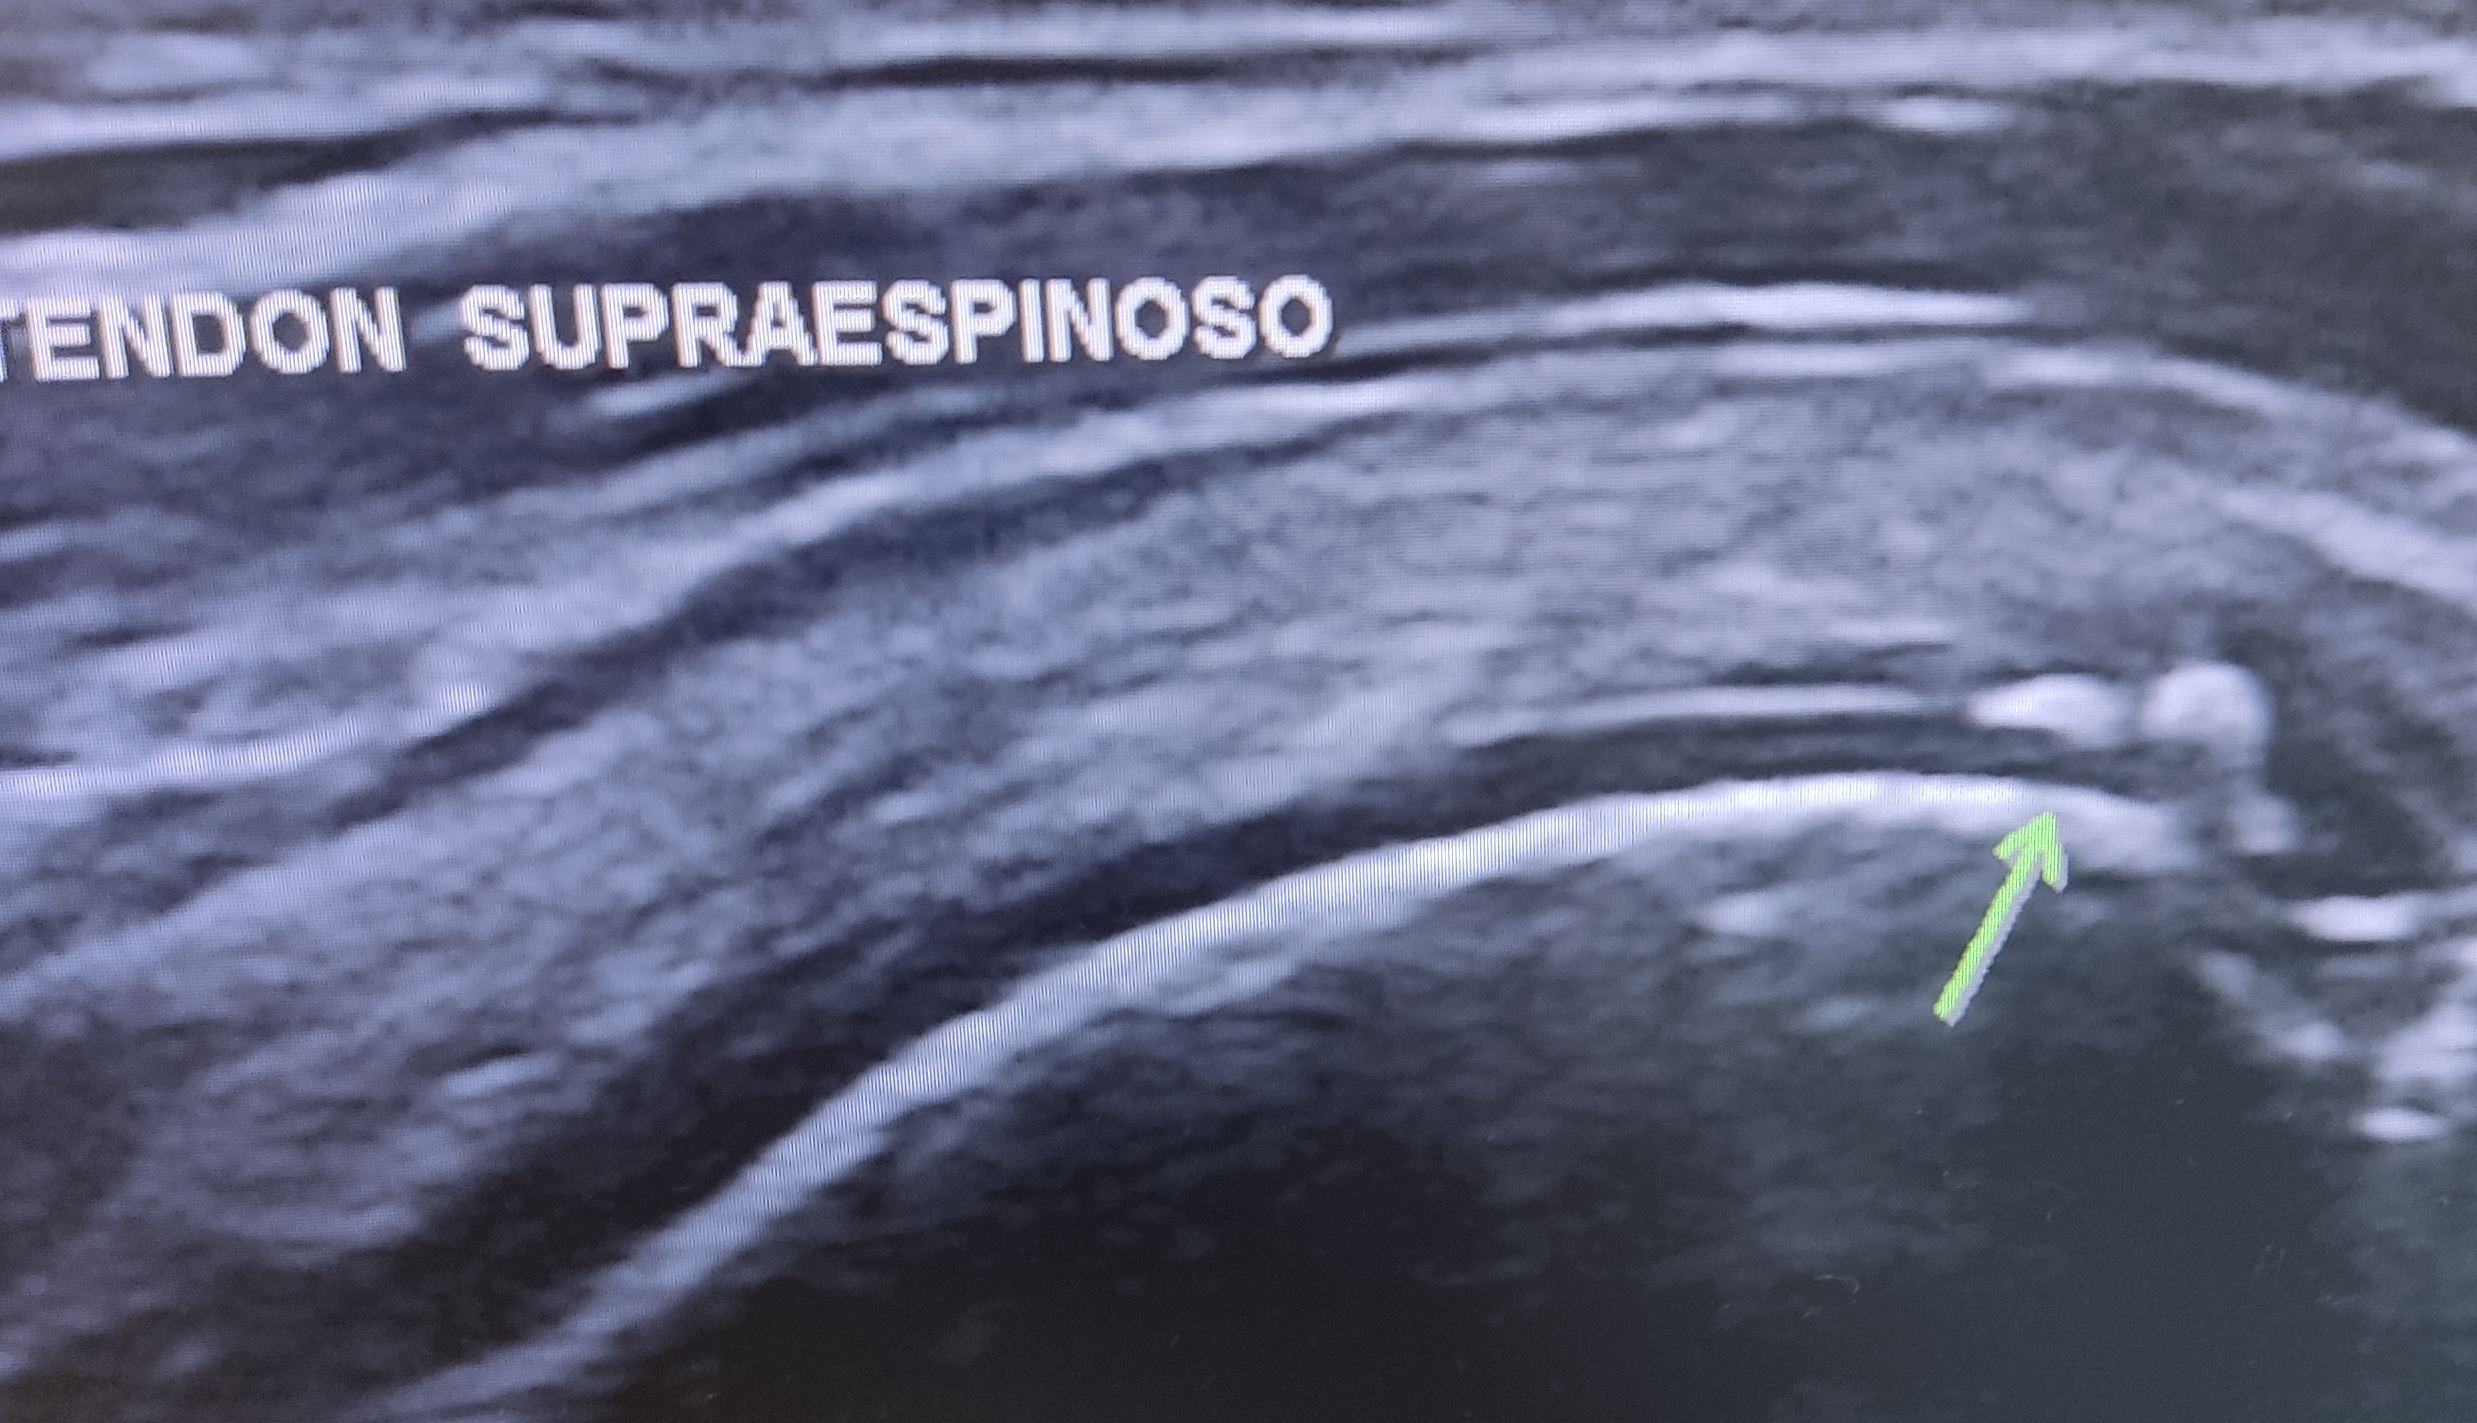

Se observan pequeñas calcificaciones en tendón supraespinoso.

En el corte transversal del supraespinoso se observan varias imágenes hipoecoicas bien delimitadas en el espesor del tendón que podrían hacer sospechar una rotura parcial intrasustancia.

En el corte transversal del supraespinoso se observan varias imágenes hipoecoicas bien delimitadas en el espesor del tendón que podrían hacer sospechar una rotura parcial intrasustancia o podrían corresponder con una persistencia de fibras musculares del supraespinoso más allá del arco óseo acromial (lo que puede ser bastante frecuente en gente joven menor de 50 años). Podemos "tirarnos a la piscina" y sugerir que tiene un supraespinoso que distalmente al acromión/ligamento coracoacromial está formado por fibras tendinosas en su mayoría, acompañadas por zonas de fibras musculares que con el envejecimiento se irán fibrosando, convirtiéndose en fibras tendinosas.